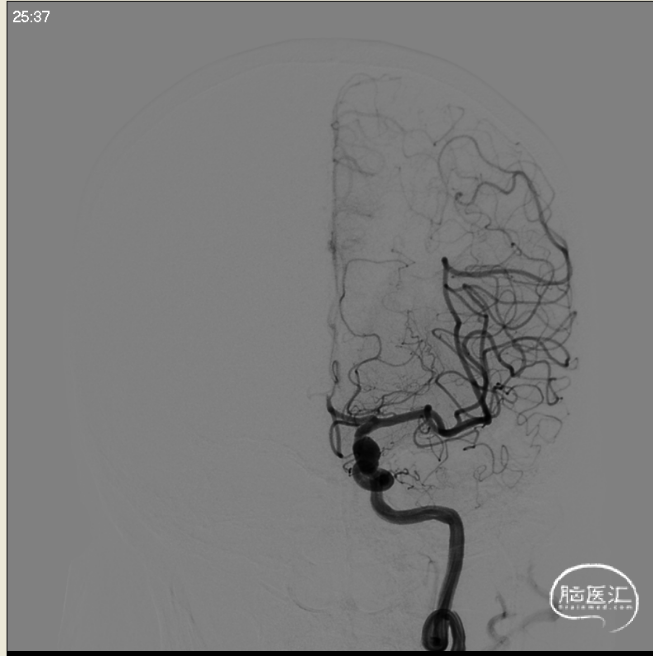

术前左侧侧位

术前左侧正位

术前右侧正位

术前右侧侧位

术前工作位

左侧3D

右侧3D

取右侧股动脉为穿刺点,Seldinger法穿刺成功后置入6F鞘。行全脑血管造影显示左侧颈内动脉眼动脉段动脉瘤,约10*7mm大小,瘤颈6.1mm。6F 90长鞘+115cm 6F SKATHI中间导管超选至左侧颈内动脉海绵窦段。